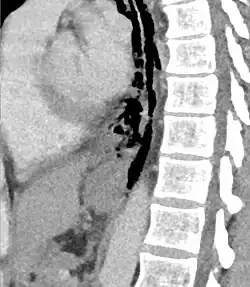

The diagnosis of Boerhaave syndrome is suggested on the plain chest radiography and confirmed by chest CT scan. The initial plain chest radiograph is almost always abnormal in patients with Boerhaave syndrome and usually reveals mediastinal or free peritoneal air as the initial radiologic manifestation. With cervical esophageal perforations, plain films of the neck show air in the soft tissues of the prevertebral space.

Hours to days later, pleural effusion(s) with or without pneumothorax, widened mediastinum, and subcutaneous emphysema is typically seen. CT scan may show esophageal wall edema and thickening, extraesophageal air, periesophageal fluid with or without gas bubbles, mediastinal widening, and air and fluid in the pleural spaces, retroperitoneum or lesser sac.

The diagnosis of esophageal perforation could also be confirmed by water-soluble contrast esophagram (Gastrografin), which reveals the location and extent of extravasation of contrast material. Although barium is superior in demonstrating small perforations, the spillage of barium sulfate into the mediastinal and pleural cavities can cause an inflammatory response and subsequent fibrosis and is therefore not used as the primary diagnostic study. If, however, the water-soluble study is negative, a barium study should be performed for better definition.